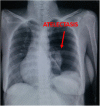

We present a rare case of 32year old female with congenital diaphragmatic eventeration female presenting in an adult. She had symptoms of intermittent dyspnea and occasional epigastric discomfort. Patient had no previous history of trauma. Physical examination showed bowel sound involving the left hemithorax. Imaging modalities confirmed the diagnosis of a congenital left diaphragmatic eventeration. Patient underwent plication of the diaphragm using the abdominal approach. Intra-operatively, the left diaphragm was attenuated. Plication was done with 1st layer of imbricating silk heavy sutures buttressed by a second layer of interrupted absorbable sutures. She post-operatively had atelectasis on the left lung. Incentive spirometry and deep breathing exercises were started with resolution of the atelectasis after 1 week post-operatively. Patient had an unremarkable post-operative stay with resolution of symptoms. There are reports that diaphragmatic eventration diagnosed even as late 70 years old, highlighting the dogma that this is an asymptomatic disorder does not need all the time surgical therapy. But we still recommend surgical therapy as soon as diagnosis is confirmed. In this patient, there was no recurrence of symptoms after a follow-up of 2 years. Whether surgery indeed improved lung functions in these vastly asymptomatic patients, these questions could be an active area of research in the long term outcomes of these patients.